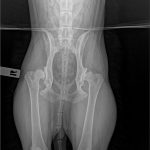

Wracamy do znanej czytelnikom Julki. TOZ ponownie zbiera fundusze na pomoc dla suczki. Julka żyje w ciągłym bólu – problemy z biodrami utrudniają jej bieganie i skakanie. U psiaka zdiagnozowano bowiem dysplazję stawów biodrowych. Dodatkowo ma silną anemię i szybko traci na wadze. Początkowo planowano przeprowadzenie operacji, ale teraz nadarzyła się inna szansa na odzyskanie zdrowia – syntetyczna wiskoproteza.

Niestety stan zdrowia suczki od początku był zły. Julka wymagała długiego procesu leczenia i opieki profesjonalistów. Na początku 2017 r. trafiła do hoteliku w Warszawie, gdzie miała mieć zapewnioną opiekę behawioralną oraz weterynaryjną. Tam zdiagnozowano u suczki ciężką dysplazję stawów biodrowych oraz bardzo silną anemię.

– Julka dziś jest piękną, łagodną 25-kilogramową kuleczką. Jej wdzięczność za nowe życie powala na kolana. Suczka odzyskała równowagę emocjonalną, ale wciąż przeszkodą są problemy natury fizycznej. Dysplazja stawów biodrowych utrudnia suni bieganie, skakanie i inne czynności. Wcześniej sądziliśmy, że będzie musiała przejść operację. Teraz znaleźliśmy nowe rozwiązanie – opowiada Karolina Lorenc.

Pomoc dla Julki czeka na nią w Gdańsku lub bliżej – we Wrocławiu. Nowa metoda Noltrex to syntetyczna wiskoproteza o właściwościach podobnych do mazi stawowej. Jej bardzo wysoka gęstość wspomaga amortyzacją stawu, zapobiegając otarciom, niwelując ból, a zawarte w niej jony srebra działają bakteriostatycznie. Wiskoproteza pomaga zachować integralność chrząstki stawowej, co jest szczególnie istotne w przewlekłych chorobach zwyrodnieniowych.